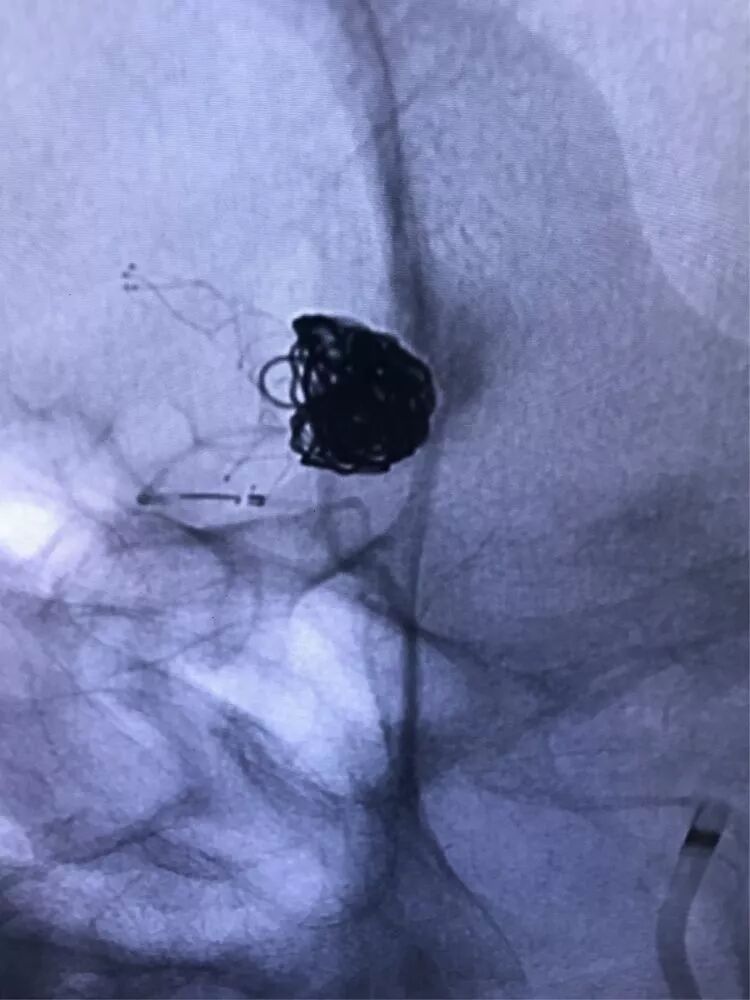

释放支架

找到支架与弹簧圈之间的切线位,继续填塞。支架很好地保护住了颈内动脉和后交通动脉

最后的填塞结果